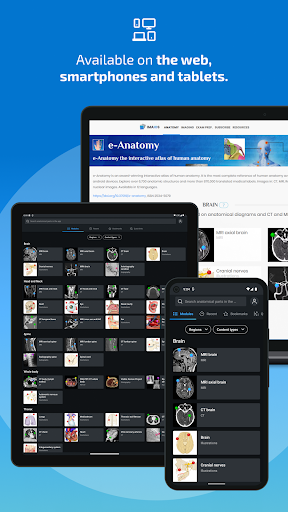

IMAIOS e-Anatomy adalah atlas anatomi manusia untuk dokter, ahli radiologi, mahasiswa kedokteran, dan teknisi radiologi. Dapatkan cuplikan lebih dari 26.000 gambar medis dan anatomi secara gratis sebelum berlangganan atlas anatomi manusia terperinci kami.

e-Anatomy didasarkan pada atlas daring IMAIOS e-Anatomy yang telah memenangkan penghargaan. Bawalah referensi anatomi manusia terlengkap, ke mana pun Anda pergi, di perangkat seluler atau tablet Anda.

HARGA aplikasi termasuk akses ke semua modul adalah 124,99$ per tahun. Langganan ini juga memberi Anda akses ke e-Anatomy di situs web IMAIOS.